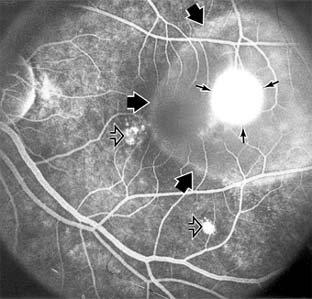

Central serous chorioretinopathy is characterized by serous detachment of the sensory retina as a consequence of focal leakage of fluid from the choriocapillaris through a defect in the retinal pigment epithelium (Figures 10-2 and 10-3). This disease typically affects young to middle-aged men and may be related to life stress events. Most patients present with the sudden onset of blurred vision, micropsia, metamorphopsia, and central scotoma. Visual acuity is often only moderately decreased and may be improved to near-normal with a small hyperopic correction.

Figure 10-2

Figure 10-2: Central serous chorioretinopathy with sensory retinal detachment (arrows) extending into the fovea.

Figure 10-3

Figure 10-3: Fluorescein angiogram of central serous chorioretinopathy shows active disease with both a retinal pigment epithelial detachment (small arrows) and a sensory retinal detachment (large arrows). Two foci of inactive disease (open arrows) are also present.